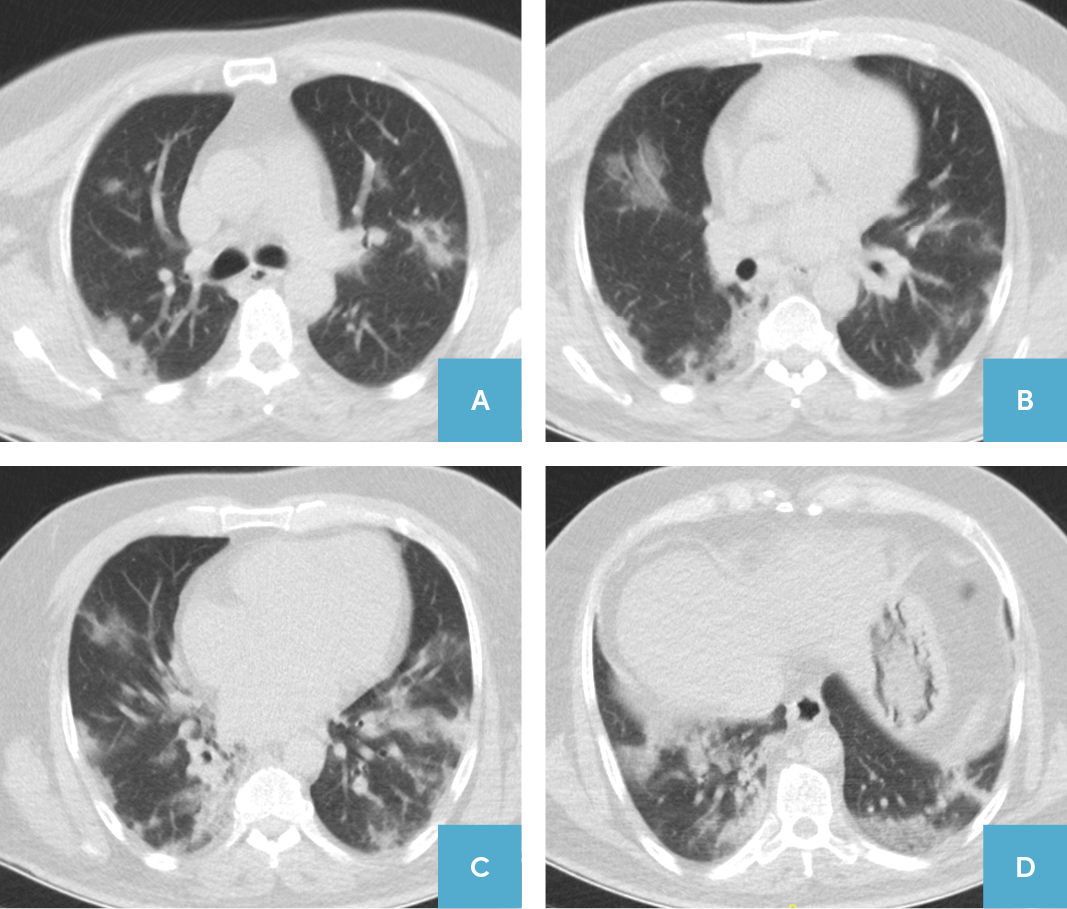

51 yaşında, sağlık çalışanı olan erkek hasta, kuru öksürük ve yaygın halsizlik şikayeti ile Kayseri Şehir Hastanesi Pandemi Polikliniği’ne başvurmuş ve COVID-19 öntanısı ile pandemi servisine yatırılmıştır. Bilinen 6 yıldır T2DM tanısı olan hasta, metformin (2000 mg/gün) kullanıyor olup başka ek hastalığı ve ilaç kullanım öyküsü yoktu. Yatışında kaydedilen kan basıncı 110/60 mm Hg, nabız 112 atım/dk, solunum sayısı 20 soluk/dk, ateş 37.2oC ve pulse oksimetre ile ölçülen oksijen satürasyonu %98 idi. Kan tetkik sonuçlarında; beyaz küre 3070 (4500-10000) µL/mm3, hemoglobin 17.6 (13-17) g/dL, trombosit 138000 (150000-450000) µL, nötrofil 2160 (1800-7500) µL, lenfosit 630 (800-3200) µL/mm3, BUN 14 (6-20) mg/dL, kreatin 0.95 (0.7-1.2) mg/dL, AST 49 (0-40) U/L, ALT 74 (0-41) U/L, CRP 4.5 (0-5) mg/dL, D-dimer (FEU) 350 (0-500) µg/L, glikoz (yatış anı, rastgele) 307 (70-200) mg/dL, HbA1c %9.1 (<6.5) olarak tespit edilmiştir. Kontrastsız toraks bilgisayarlı tomografi görüntülemesinde, her iki akciğerin tüm loblarında yaygın olarak santral ve periferik buzlu cam görünümleri ve bazılarında kaldırım taşı değişimi izlenmiştir (Resim 1). Hastaya, T.C. Sağlık Bakanlığı COVID-19 Tedavi Rehberi’ne göre; enoksaparin 0.6/gün IU subkutan, hidroksiklorokin tablet (başlangıç 800 mg/gün, idame 400 mg/gün) ve azitromisin tablet (başlangıç 500/gün mg, idame 250 mg/gün) başlanmıştır.